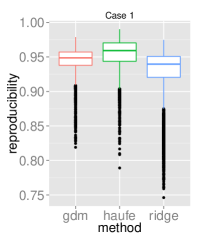

To assess the discriminative performance and reproducibility of the compared methods under varying confounding scenarios, we used the ADNI dataset. We simulated four distinct training scenarios in increasing potential for confounding effects: Case 1: AD + CN subjects, mean age balanced, Case 2: CN + AD, mean age balanced, Case 3: AD + CN, oldest ADs, youngest CNs, Case 4: CN + AD, oldest ADs, youngest CNs.

All models had their respective parameters () cross-validated in an inner fold before performing out-of-sample prediction on a left out test set consisting of equal numbers of AD and CN subjects with balanced mean age. Furthermore, the inner product of training model parameters was compared between folds to assess the reproducibility of models. Training and testing folds were shuffled 100 times to yield a distribution.

The prediction accuracies and the model reproducibility for the above cases are shown in figure 2. The results demonstrate that while GDM is not a purely discriminative model, its predictions outperformed ridge regression in all four cases. Regarding reproducibility, the Haufe et al. (2014) procedure yielded the most stable models since it yields a purely generative model. However, GDM was more reproducible than ridge regression.